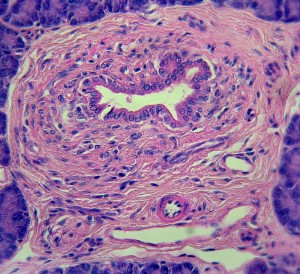

Nya hjärtat ses som en fiende

För den obotligt hjärtsjuke är det nya hjärtat efterlängtat. Men kroppen reagerar mot allt utom mot sig själv. Främlingar attackeras, oavsett om det är ett transplanterat organ eller en bakterie. Hjärttransplantationer är därför beroende av…